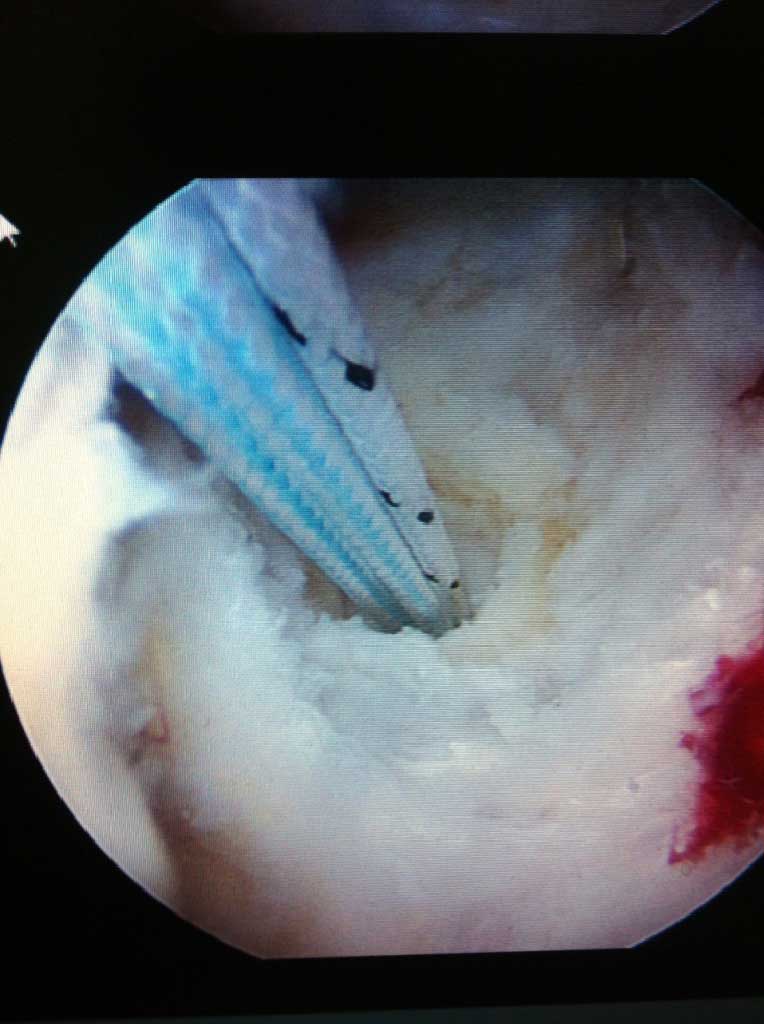

Wird die Indikation zur Sehnennaht / Rekonstruktion der gerissenen Sehnen gestellt, so wird die Operation in unseren Händen ausschließlich arthroskopisch (Schlüsselloch Operation) durch 3 - 6 kleinen Stichinzisionen (3-4mm) durchgeführt. Dieses operative Verfahren ist maximal zu den schulterumgebenden  Weichteilen schonend.

Je nach Alter, Verletzungsmuster, Anzahl der Luxationsereingnisse und weiteren Faktoren, wird eine schulterstabilisierende Operation indiziert und empfohlen. Diese führen wir ebenfalls ausschliesslich arthroskopisch

(Schüsselloch Operation) durch. Innerhalb von 15 - 30 min wird dabei der knorpelige Ring (s.g. Labrum) auf den knöchernen Pfannenrand mit speziellen Anker und Fäden wieder zurück befestigt.